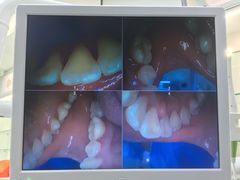

• 牙博士口腔品牌连锁(杨浦店)

• -牙博士口腔品牌连锁(杨浦店)

徐大仔 | 21-08-20